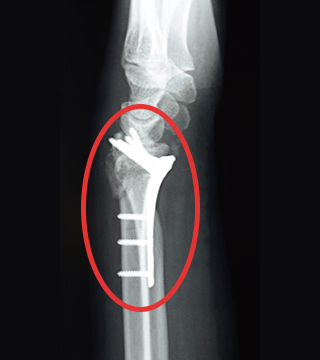

注目ポイント2 橈骨に沿う“逆位相”を採用した世界初のプレート

骨は平面でなく、とくにプレートで固定したい部分は逆向きの傾斜となっています。 ハイブリッドロッキングプレートは、解剖学的な遠位・近位の逆 位相の捻れを再現しており、骨表面と良好な適合性を持つことができます。